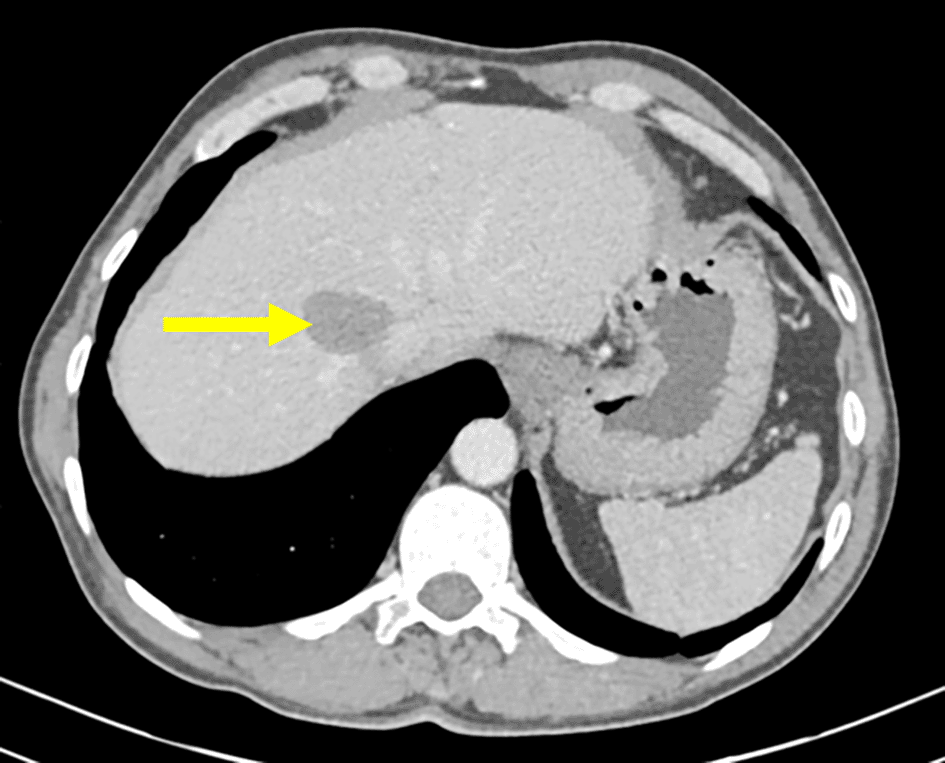

The patient was followed up at the department of abdominal surgery for a multiple organ hydatidosis including 13 hydatid cysts: the lungs, the liver ( Figure 1), the left heart ventricle, the left kidney (Figure 2), the abdomen cavity, the muscles (psoas, adductors), and the subcutaneous gluteal area. Those cysts were already treated surgically (Table 1). The patient has received oral Albendazole 400 mg twice-daily for 2 years.

Heart involvement is uncommon and accounts for less than 0.5% of the cases, it is usually a part of disseminated infection.4 This localization is potentially fatal without surgical treatment but thanks to the improvement in surgical techniques, its morbidity has declined drastically. The patient underwent open heart surgery to remove a left ventricular wall cyst. Post-surgical echocardiography revealed no local recurrence and no abnormalities.

Invasion of the myocardium usually occurs hematogeniously through the coronary arteries and since the majority of the population have a left dominant circulation, the left ventricle is the most commonly involved part of the heart (60%),4 Another possible explanation is the dissemination from the lungs either following a pulmonary vein rupture and migration of the cysts5 or by a direct contact with hydatid cysts originating from the lung.6